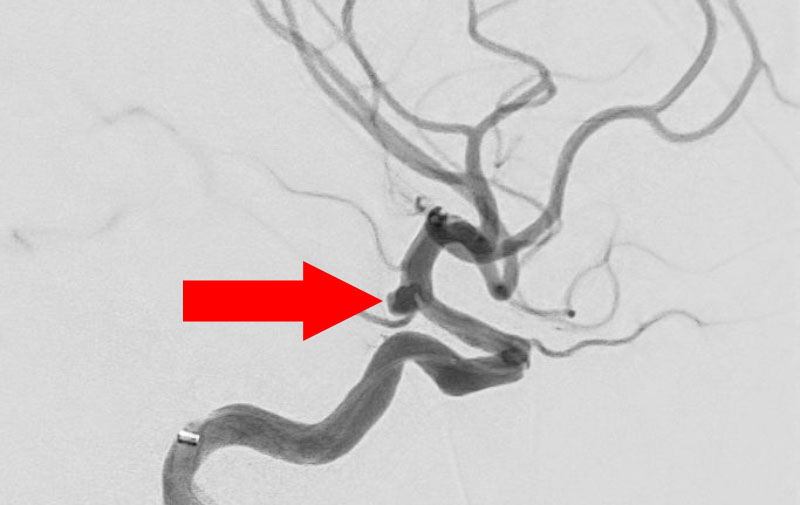

No.1602 手術後